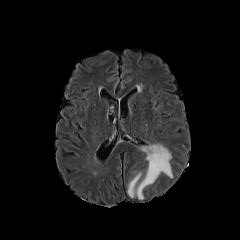

Refer to caption

(a) Conv1 Feature

(b) Conv1 Feature

(c) Deconv2 Feature

(d) Deconv2 Feature

Figure 6: A visualization of two features of the generator 𝒢A2Nsubscript𝒢A2N\mathcal{G}_{\rm{A2N}} on the BratS MRI data. The tumor is gradually identified.

We show feature maps of the generator 𝒢A2Nsubscript𝒢A2N\mathcal{G}_{\rm{A2N}} on a BratS MRI data in Figure 6, which clearly shows that the generator 𝒢A2Nsubscript𝒢A2N\mathcal{G}_{\rm{A2N}} tries to capture and work on the lesion regions with the global shortcut connection.